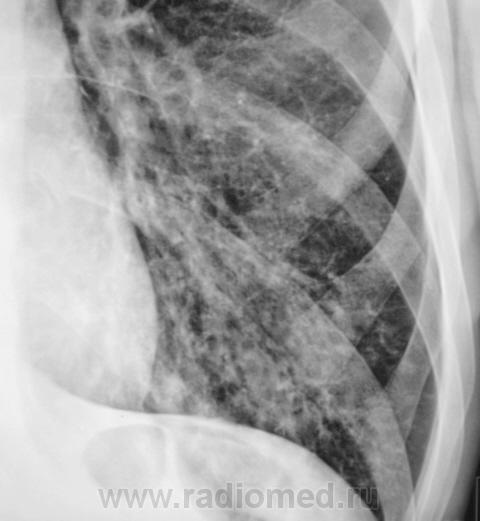

Пациент направлен на рентгенографию ОГК с диагнозом  - "Левостороняя пневмония".

Анамнез стандартный. Ранее неоднократно страдал обострениями хронического бронхита. Сейчас вот не нашутку занемог - температура до 38, откашливает мокроту, кашель продуктивный.

Диагноз левосторонней нижнедолевой С10, С9 сементарной пневмонии наверное будет верным, а с учётом фона- с наличием бронхоэктазов.